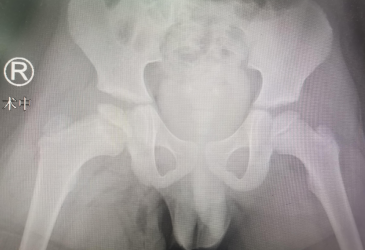

术中X线

“股骨头缺血坏死”这种疾病一般发现确诊时就要诊治,症状表现为髋关节压痛明显,被动内旋时疼痛明显,X线的变化主要是干骺端、骺板及髋臼的改变,可能发现股骨头变形,核磁共振对于股骨头内、外侧显影更为清晰。治疗方式早期一般有卧床休息、牵引治疗、双下肢内旋位管型石膏固定,后期为恢复股骨头血供,使股骨头形态发育正常,可选择股骨头钻孔引流、髂腰肌松解术来治疗。

王泺镔主治医师介绍,来院就诊的这几个小朋友都是股骨头缺血坏死,这是一种常见于2-12岁(6-8岁为发病高峰)的一种疾病,不少患儿因症状轻微而未就诊。患儿常有跛行,有时诉髋部、膝部或大腿疼痛。检查发现患髋活动受限(特别是外展和内旋受限)以及大腿肌肉轻度萎缩。此种疾病最主要的影响就是对平时走路的影响,会导致髋外旋和内旋明显,屈髋时下肢有被迫性外旋的动作,股骨头被破坏。